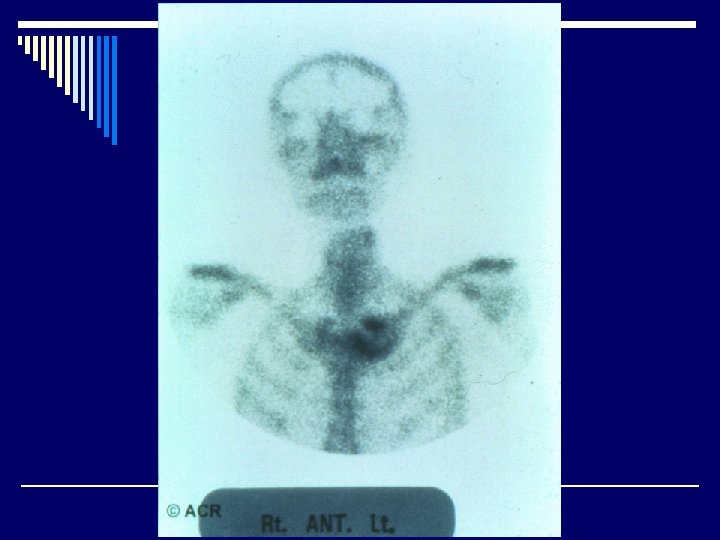

Radiological features o Joint effusion o Erosion o Joint space narrowing o Joint deformity o Osteoporosis o Bony ankylosis